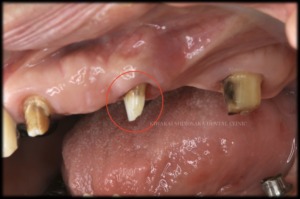

詳しく診査・診断した結果、他院で作製された義歯の金具を支えていた歯が破折していたため、義歯装着時に掛かる負荷によって痛みが生じていたことがわかりました。

しかし、問題のある歯は仮歯の真ん中に位置しており、この歯を無くしてしまうと連結した仮歯を支える歯が左上1と7だけとなり、間に歯がひとつも無い状態となるため、維持していくのが難しくなることが懸念点でした。

患者さまとご相談の結果、仮歯の維持を優先し、抜歯の前にインプラント2本の埋入から進めることにいたしました。治療箇所の治癒を待った後、インプラントの頭出しの手術を行う際に、主訴である歯(左上4)の抜歯を行いました。